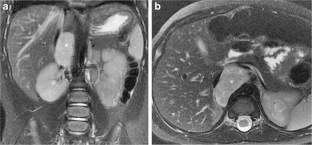

Fig. 2